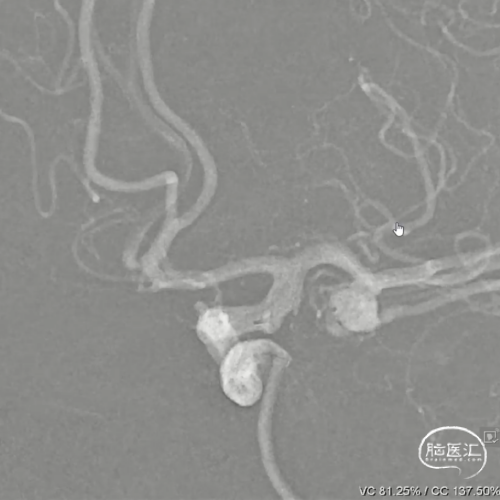

右侧后交通段动脉瘤,大小约13.36mm*13.26mm,瘤体上有子囊形成,床突段至后交通段血管稍狭窄,脉络膜前动脉距瘤颈部有一定距离。

Headway 17微导管塑形后置入动脉瘤瘤体内,半释放18mm*44cm complex弹簧圈成篮,半释放3.5mm*20mm LVIS支架保护瘤颈后完全释放18mm*44cm complex弹簧圈成篮,后依次释放6枚弹簧圈栓塞动脉瘤,最后一枚弹簧圈释放完成后造影,后交通动脉瘤少量造影剂进入,完全释放支架,右侧后交通动脉瘤瘤体内极少量造影剂进入,子囊不显影,Raymond分级3级,同时造影见各主干级分支血管显影良好,遂退出系统。